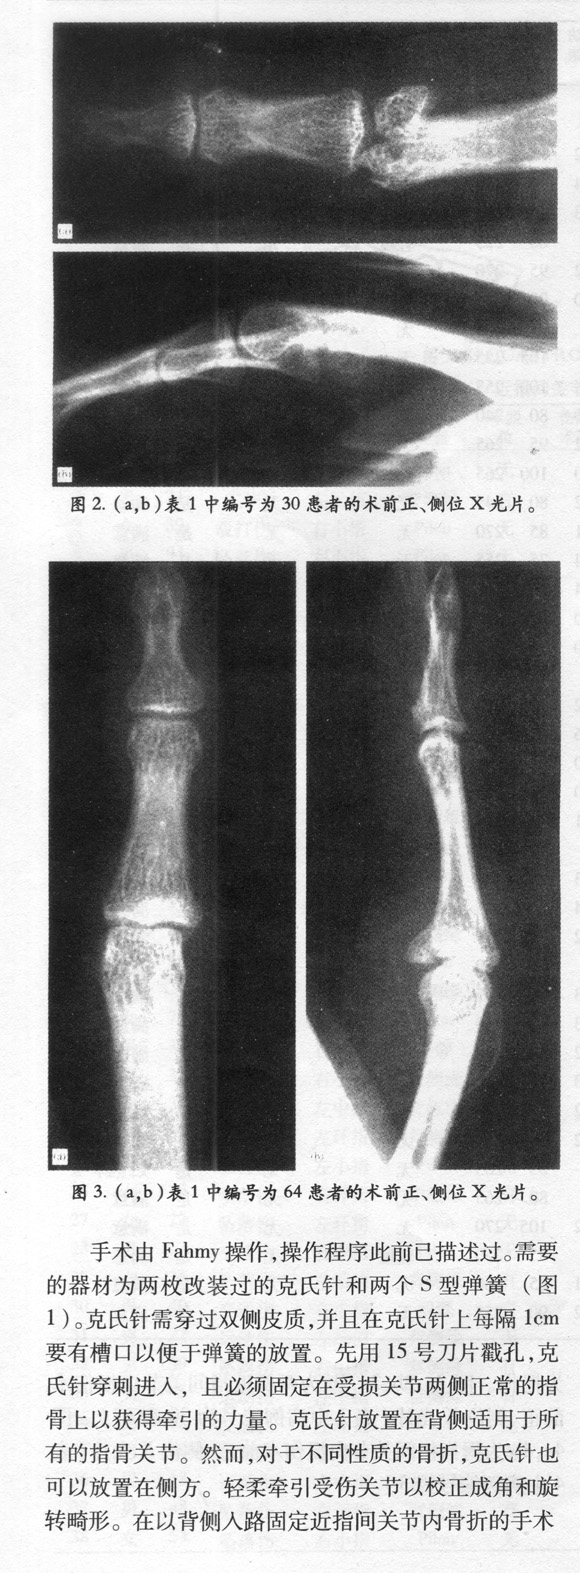

应用S-QUATTRO治疗急性指骨关节内骨折